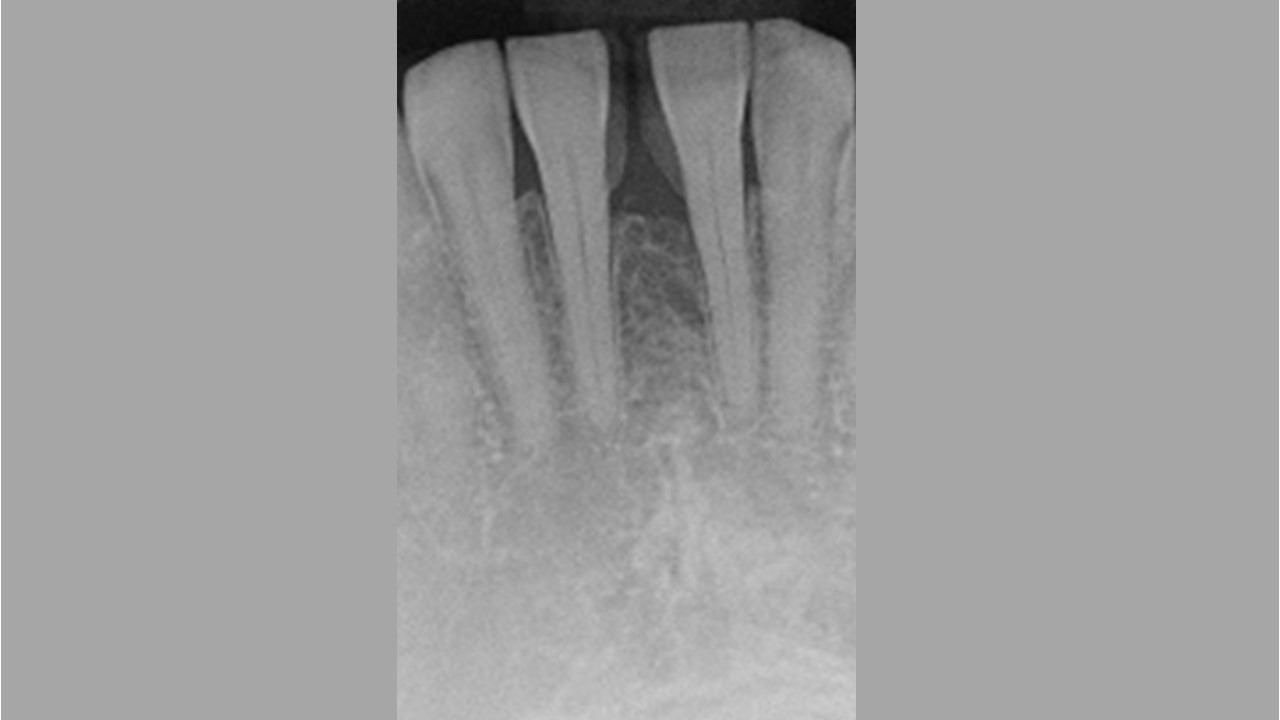

02/13 - Baseline radiograph.

Wide intrabony defect treated with the modified papilla preservation flap in conjunction with Straumann® Emdogain® and autogenous bone - Dr. B. Molnar